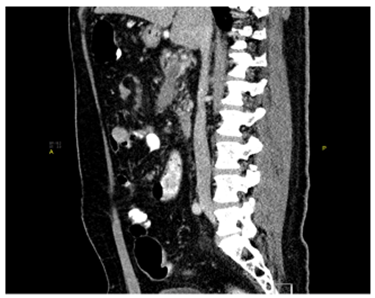

Acute mesenteric ischemia refers to the sudden onset of intestinal hypoperfusion, one cause of which can be mesenteric venous occlusion. Acute superior mesenteric vein (SMV) and portal vein (PV) thrombosis can be a complication of hypercoagulable, inflammatory, or infectious states. It can also occur as a complication of medical or surgical intervention. Management of mesenteric and portal vein thrombosis includes both operative and nonoperative approaches. Operative interventions include thrombectomy with thrombolysis; this is often employed for patients who present with signs of peritoneal irritation. Nonoperative approaches can be either noninvasive or invasive. Treatment with anticoagulation has been shown to be efficacious, and recanalization can be achieved (Figure 1).

50-year-old gentleman previously healthy, non smoker, non alcoholic presents to Emergency Department (ED) with left hypochondrial colicky non radiating pain, aggravated by heavy meal for five days, and associated with severe diaphoresis and nausea. He sought for medical advice twice and treated first time as a case of gastritis, and on second visit basic blood work including CBC, U&E, Lactate, LFTs were within normal range and Ultrasound showed no abnormalities, and discharged on Paracetamol and antacids. Patient did not improve inspite of compliance with the prescribed medications and presented to our ED by the same complaints, on examination, patient was stable vitally, with soft non-tender abdomen and normal bowel sounds. He underwent comprehensive study including Ct abdomen with contrast which reveled: Thrombosis of the superior mesenteric vein and its branches noted. The thrombus is seen extending, through the main portal vein partially occluding its lumen, to involve the splenic vein and right portal vein as well (Figure 2). Enoxaparin was started for him, work up for thrombophilia was sent, GI consultation was made to arrange for OGD (Oesophago–gastro-Dudenoscopy), looking for malignancy which revealed erosive gastritis with significant modularity, CLO test was negative, tumor markers were sent (CA 125- CA19-9 CEA) were normal, homocysteine 13.9 (high), B12=111 (low), during his stay at hospital patient has no complain, and his physical exam was normal.

Patient discharged from hospital with diagnosis of homocystienemia, B12 deficiency, and normal thrombophilia work up. With plan to start rivaroxiban 20mg PO OD, frequent follow-up at clinic. After 6 month ct abdomen with contrast repeated and revealed recanalization of the portal vein and splenic vein with partially recanalization of the superior mesenteric vein which is surrounded with fat standing and multiple sub centimeter of lymph nodes.